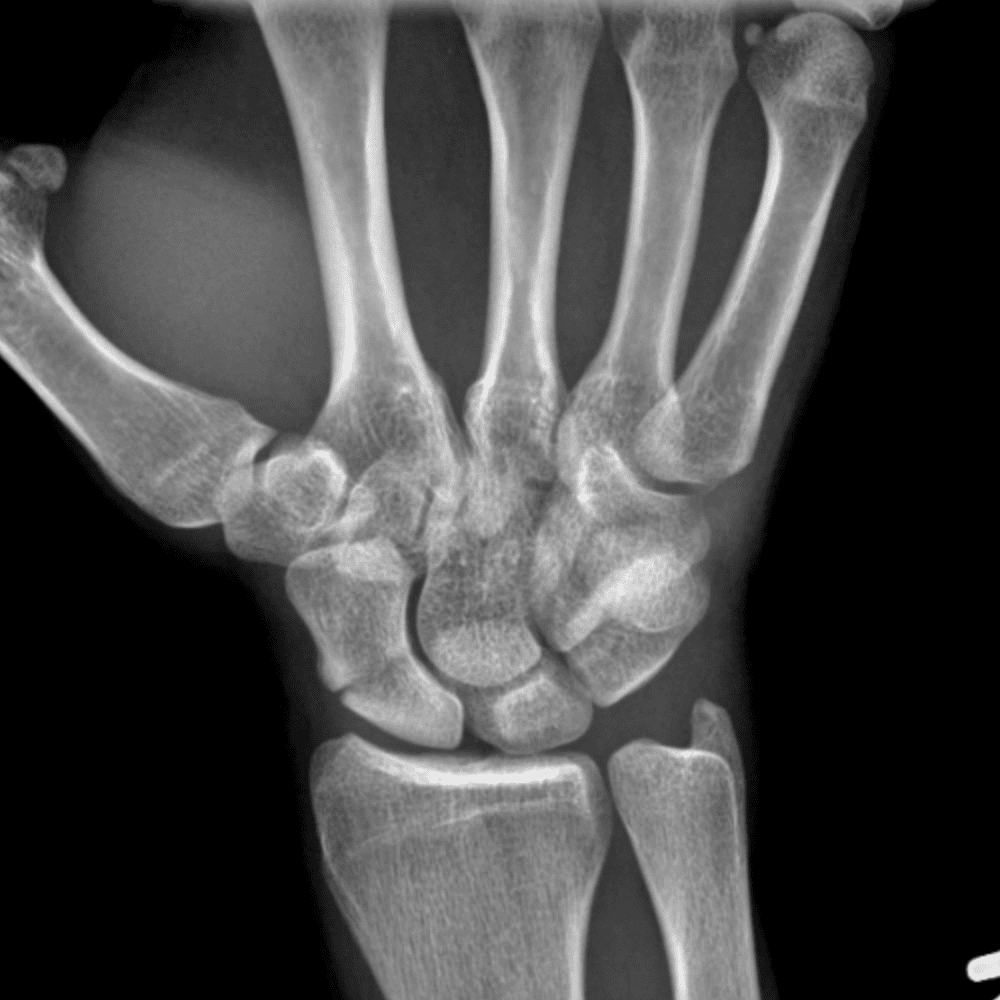

Simuliert den Dienst durch subtile oder schwierige Fälle und einige Normalbefunde.

30 Fälle